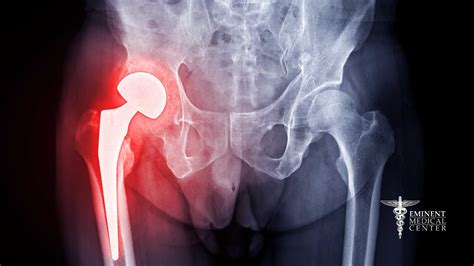

Patient undergoing physical therapy for hip recovery

Recovery following Hip Resurfacing Surgery requires patience and dedication to a structured physical therapy plan. Most patients spend a few days in the hospital, during which time they begin guided movement to prevent stiffness. The focus in the first few weeks is on managing inflammation, protecting the surgical site, and learning how to move safely without compromising the hip.